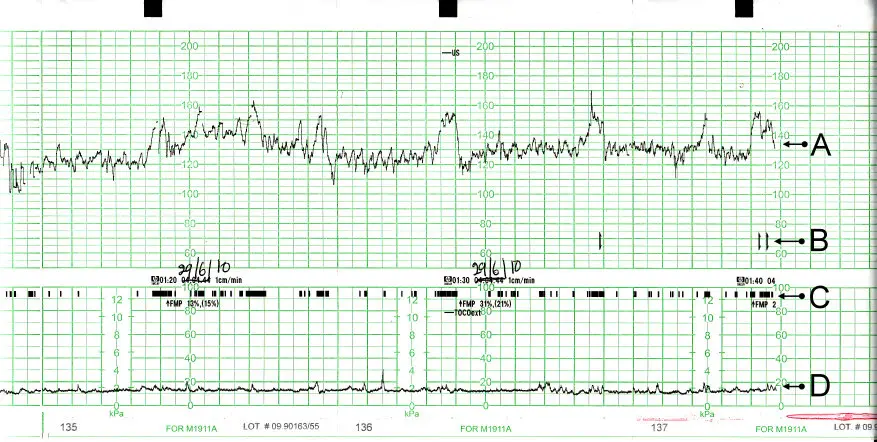

Die Daten, die von den Sensoren aufgezeichnet werden, werden auf einem Papierstreifen oder einem Bildschirm angezeigt. Die obere Kurve auf dem Papierstreifen zeigt die Herzfrequenz Ihres Babys, während die untere Kurve die Wehentätigkeit darstellt.

Die CTG-Werte werden von Ihrem Arzt oder Ihrer Hebamme ausgewertet. Sie achten dabei auf verschiedene Faktoren, wie zum Beispiel:

- Grundfrequenz: Wie viele Herzschläge pro Minute hat Ihr Baby?

- Bandbreite/Variabilität: Schwankt die Herzfrequenz Ihres Babys?

- Dezelerationen: Verlangsamt sich die Herzfrequenz Ihres Babys regelmäßig?

- Akzelerationen: Verschnellert sich die Herzfrequenz Ihres Babys regelmäßig?

Herzfrequenz Ihres Babys

Die normale Herzfrequenz eines Babys liegt zwischen 120 und 160 Schlägen pro Minute. Während der Geburt kann die Herzfrequenz Ihres Babys jedoch schwanken. Es ist normal, dass die Herzfrequenz Ihres Babys während der Wehen sinkt und nach der Wehe wieder ansteigt. Dies ist ein Zeichen dafür, dass Ihr Baby auf die Wehen reagiert und eine gesunde Versorgung erhält.

Wehentätigkeit

Die Wehentätigkeit wird auf dem CTG als eine Reihe von Wellen dargestellt. Jede Welle entspricht einer Wehe. Die Höhe der Welle zeigt die Stärke der Wehe an, während die Zeit zwischen den Wellen die Häufigkeit der Wehen anzeigt.